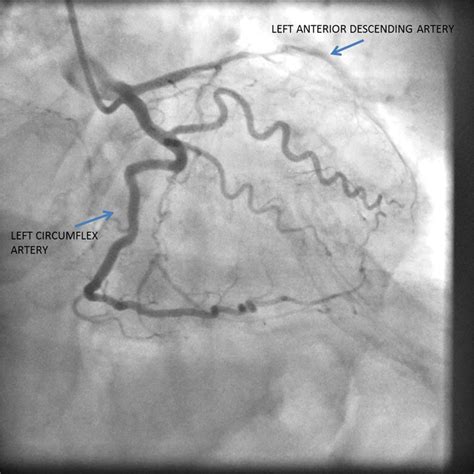

The Left Circumflex Artery originates from the left main coronary artery, which bifurcates shortly after leaving the aorta. While the left anterior descending (LAD) artery travels down the front of the heart, the LCx takes a different path, winding around the left side of the heart within the atrioventricular groove. This strategic positioning allows it to supply blood to critical areas that other vessels might not reach.

Cardiac Catheterization The gold standard for directly visualizing the artery via angiography.

Left Circumflex Artery